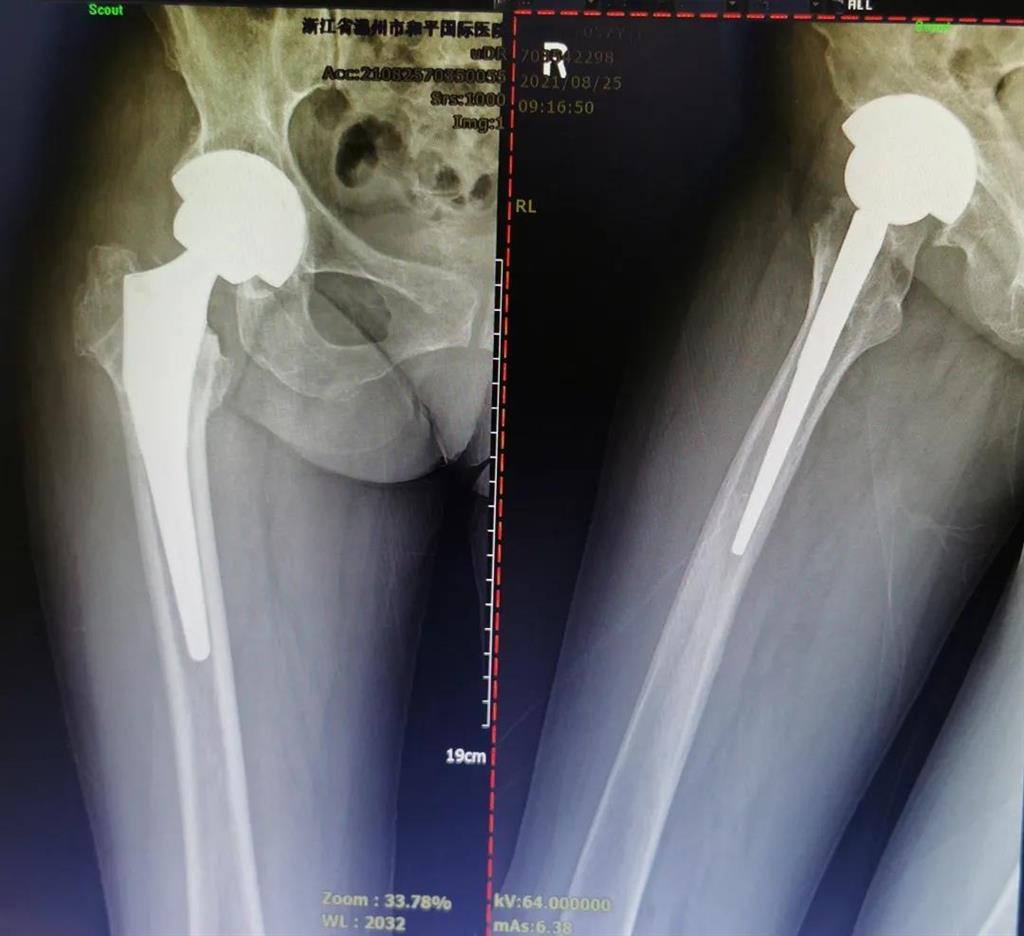

(△做完“右股骨頸全髖關(guān)節(jié)置換術(shù)”后的影像)